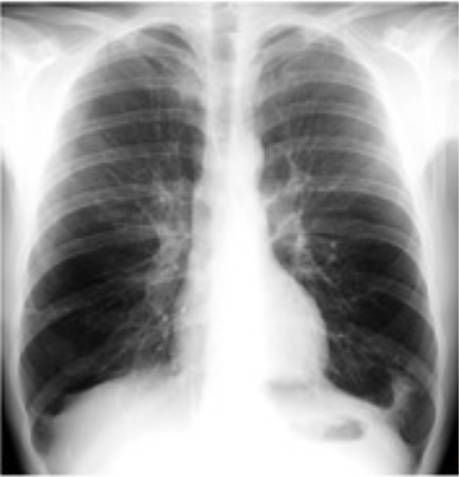

胸部X线

在正位胸片上,局限性阻塞性肺气肿表现为肺野局限性透明度增加,其范围取决于阻塞的部位。一侧肺或一个肺叶的肺气肿表现为一侧肺或一叶肺的透明度增加,肺纹理稀疏,纵隔移向健侧,病侧横膈下降。弥漫性阻塞性肺气肿表现为两肺野透明度普遍性增加,常有肺大疱出现,肺纹理稀疏。疾病晚期,肺纹理进一步变细减少、肺野透明度明显增加,胸廓前后径及横径均增大,肋间隙增宽,横膈低平且活动度减弱。心影狭长呈垂位心型,中心肺动脉可以增粗、外围肺血管纹理变细,严重者出现肺动脉高压及肺心病。